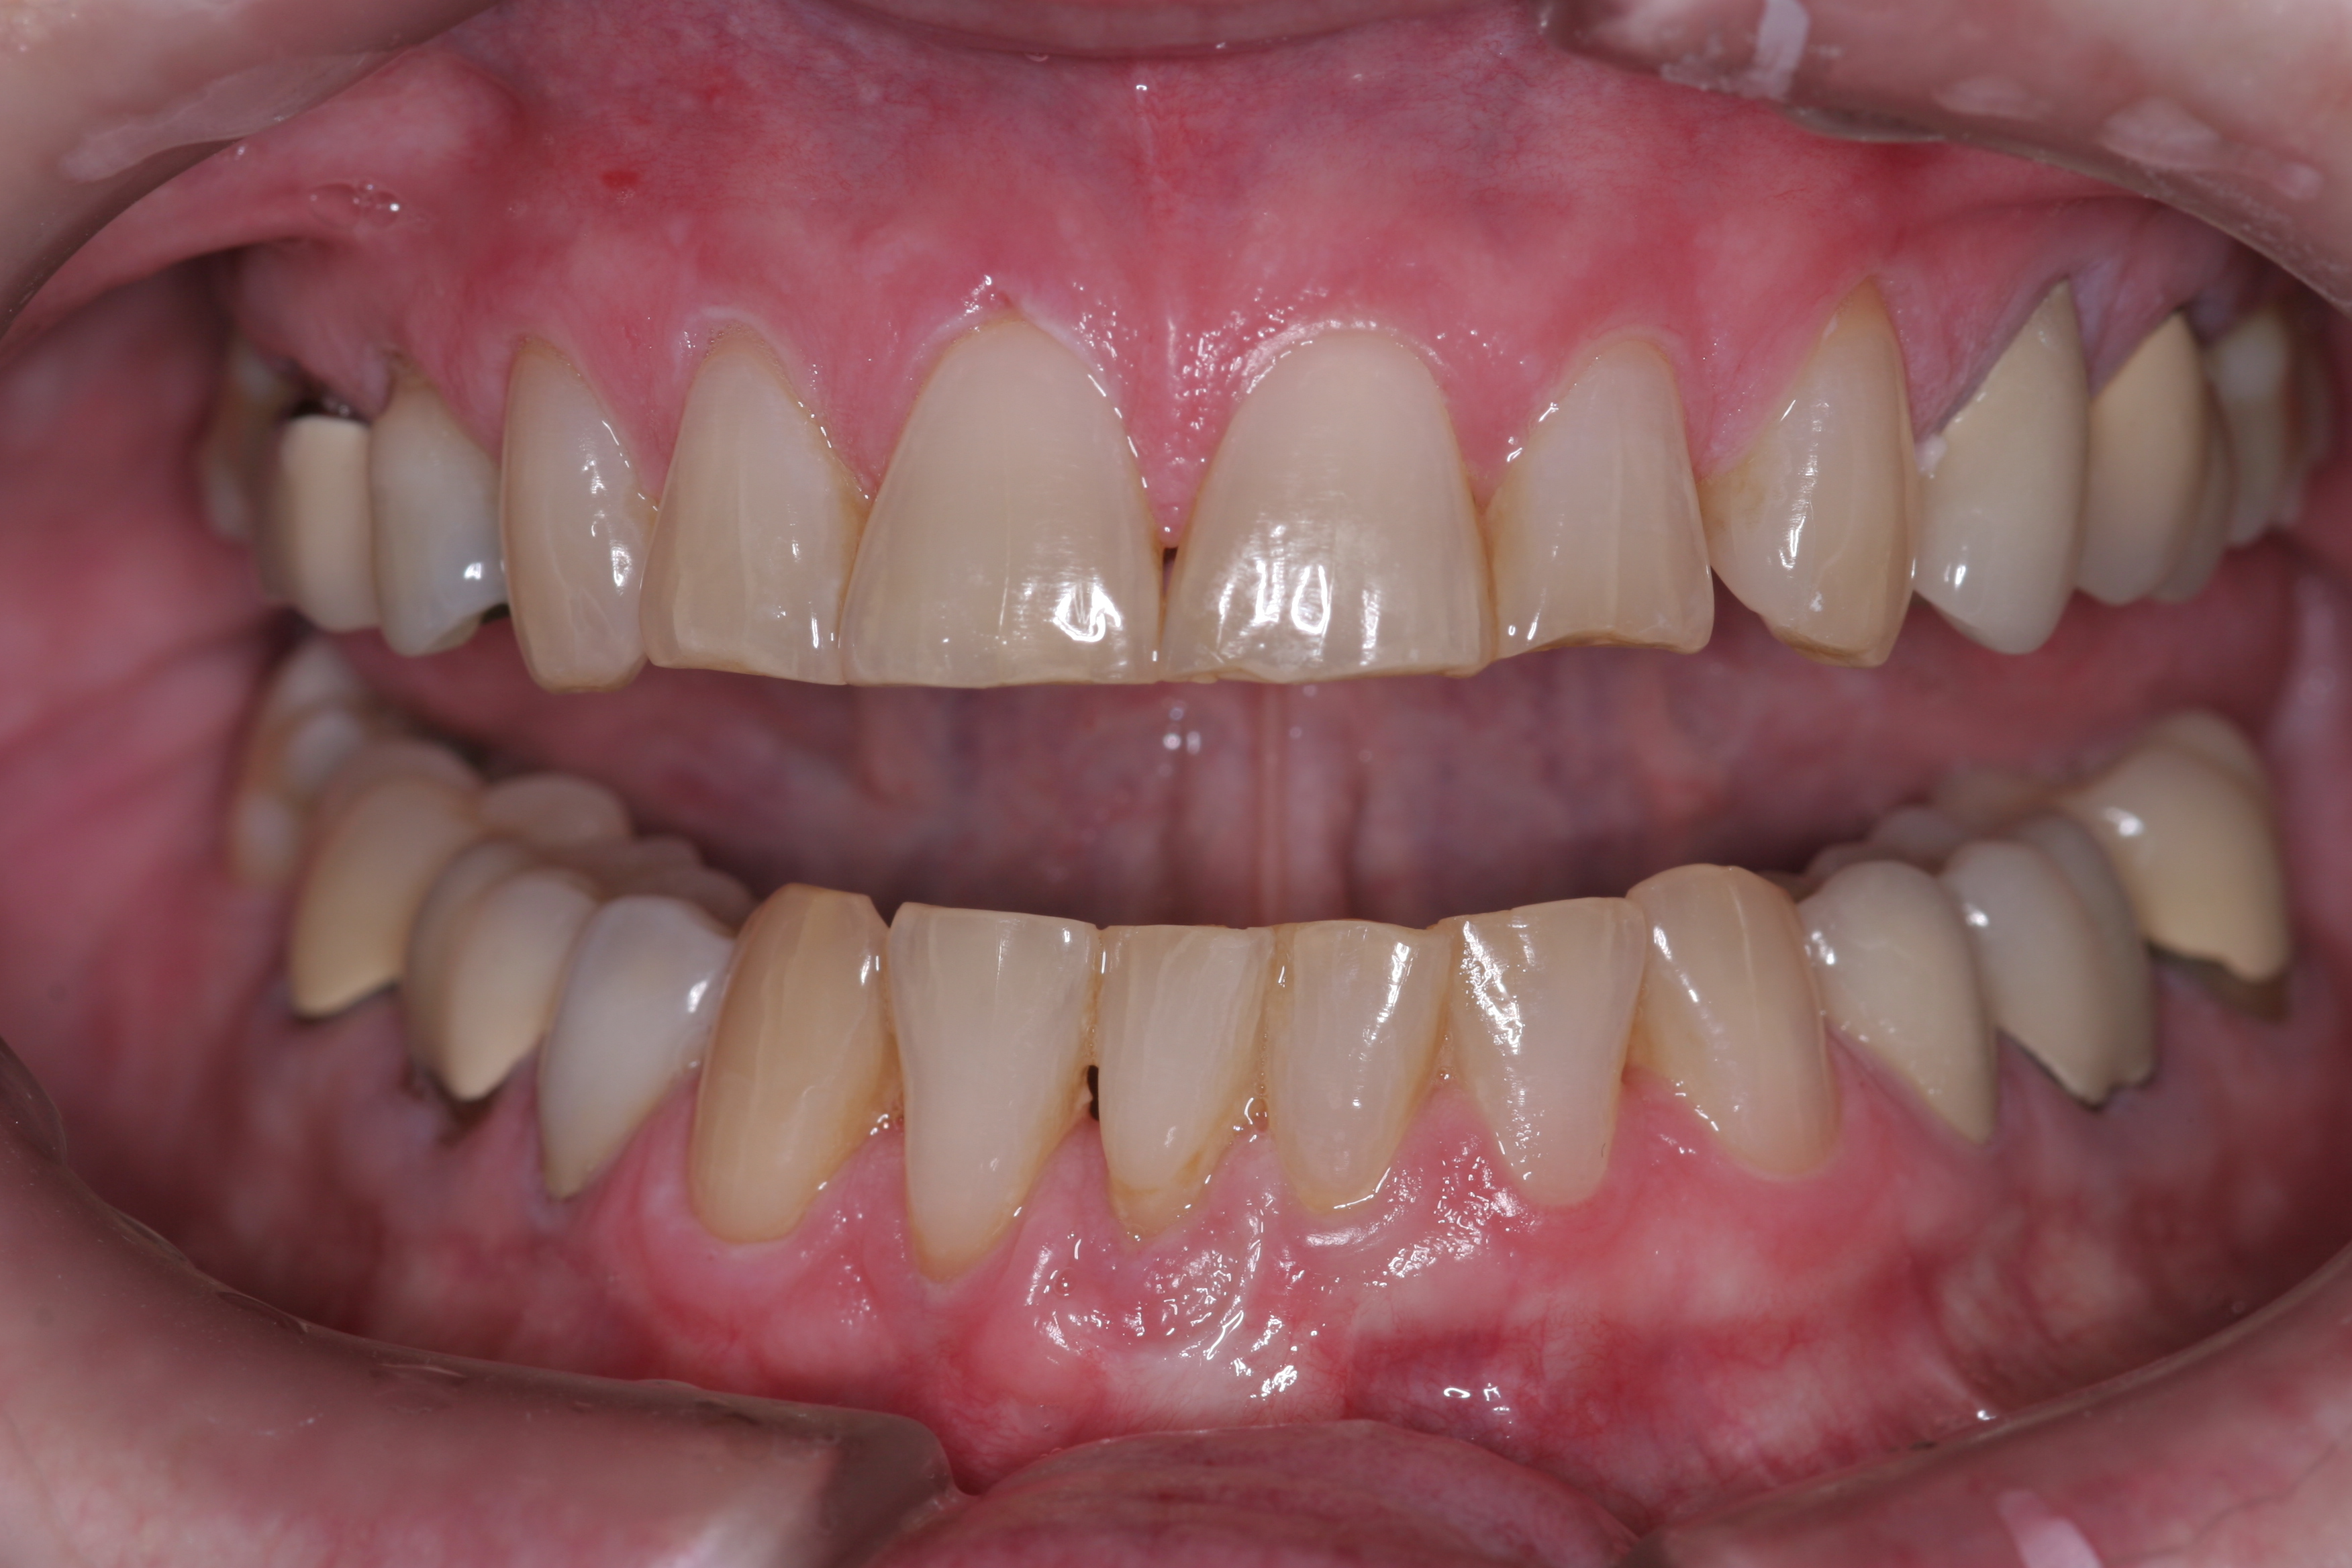

(11.) A patient presented with advanced generalized wear of her anterior teeth, and was displeased with their overall appearance because of their color and wear.

Figure 11

(12.) A patient presented with advanced generalized wear of her anterior teeth, and was displeased with their overall appearance because of their color and wear.

Figure 12

A patient presented with advanced generalized wear of her anterior teeth (Figure 10 and Figure 11). She was displeased with their overall appearance because of their color and wear (Figure 12). A complete examination was performed, revealing instability in her temporomandibular lateral poles bilaterally, sore muscles of mastication, advanced wear, a CR/MIP discrepancy, and loss of her anterior guidance due to the wear. Although the topic is beyond the scope of this article, the patient was also screened for possible sleep apnea. This included an evaluation of the Mallampati score, previous sleep therapy evaluation or treatment, snoring history, an evaluation of her neck size, her weight status, and the presence of the tonsils and their size. In every case, if this clinician suspects airway obstruction to be playing a role in tooth wear issues, the patient is referred to a sleep physician. The patient in this case displayed few apnea risk factors, and the patient’s anterior wear facets fit together like a “lock and key” pattern seen in parafunctional activity. Splint therapy was initiated to stabilize the joints and muscles. A repeatable CR position was verified through load testing. At this point diagnostic models, photographs, a CR bite record, and a facebow were taken and recorded.